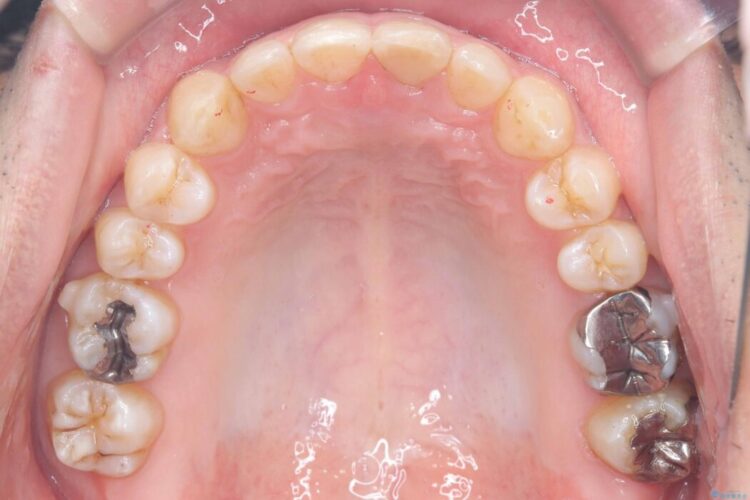

正中離開・叢生のほかに、上下の奥歯が全く咬み合わないシザーズバイトの状態も認められました。

歯の隙間とデコボコ、シザーズバイトも改善され、咬み合わせや見た目が整い、患者様にも大変ご満足いただけました。